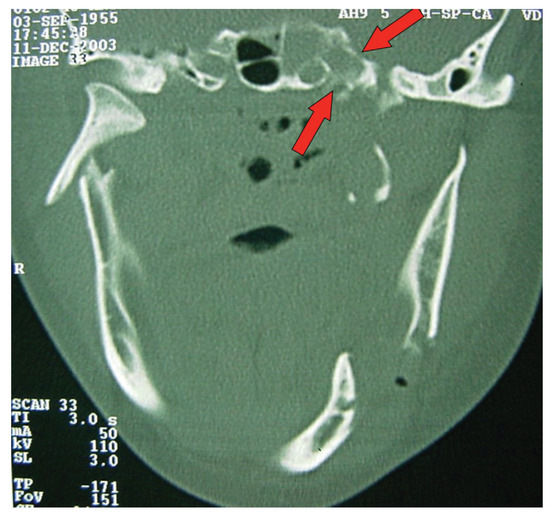

Figure 4.

CT windows with arrows highlighting fractures to the sphenoidal sinus.